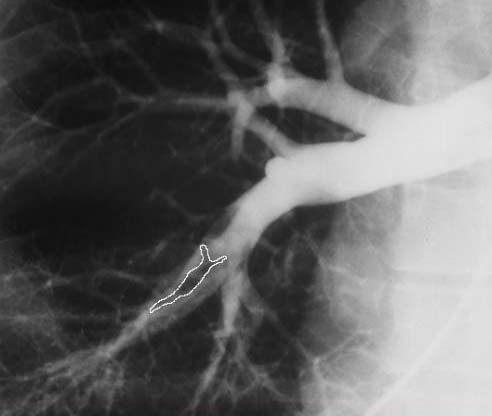

Тромбоэмболия легочной артерии на рентгеновском снимке

Ни один из методов диагностики не может дать окончательный диагноз, поэтому только комплексное использование различных методик позволит выявить признаки тромбоэмболии легочной артерии.